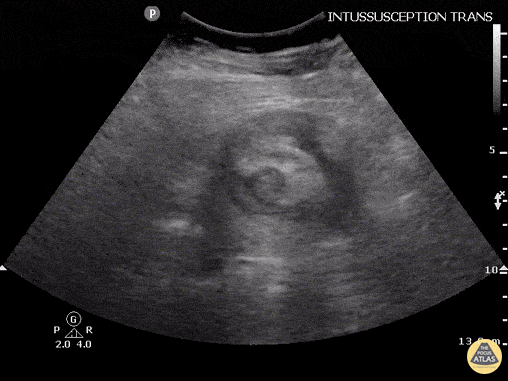

Bowel-GI - Intussusception Adult

Intussusception is typically a disease of the young (6 months to 6 years) but it can occur in adults. Adults will often present similar to bowel obstruction, with vomiting, constipation, and rectal bleeding. Ultrasound can still be used to work them up although most of the time CT will be used first. In kids, the sensitivity and specificity approach 100% but can be operator dependent. It is usually performed with a linear probe in children but in this image, a curvilinear probe was used. Justin Bowra MBBS, FACEM, CCPU Emergency Physician, RNSH et al.